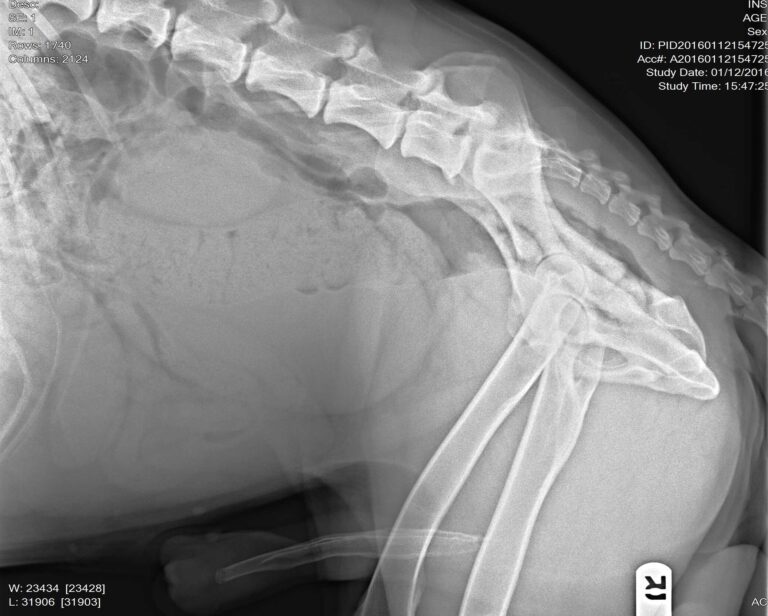

Prince, a 7 year-old unneutered German Shepherd, was not feeling his best. He’d been having trouble urinating more than small amounts at a time for a couple of days. He’d had an accident in the house, which was very unlike him. And sometimes he leaked a little urine while lying down. On physical exam, Prince’s bladder felt much distended. On his x-rays, his bladder was very full, and his prostate gland was visibly enlarged.

Benign prostatic hyperplasia (BPH) happens regularly to intact dogs, and can begin as young as 2.5 years of age. I have personally seen more cases of this in the past couple of years, as more dog owners are waiting until later to neuter or forgoing neutering altogether due to potential health benefits of keep them intact longer. Increased blood supply with hyperplasia can lead to clinical signs of blood in the urine and/or on the prepuce. The enlarged prostate may put pressure on the rectum, causing difficulty with having a bowel movement. Other than these clinical signs, affected dogs are usually normal, alert, and active. The prostate is symmetrically enlarged and is not painful. Abdominal x-rays confirm mild to moderate prostate enlargement, which may move the rectum and push the bladder forward in the abdomen. Definitive diagnosis is only possible by biopsy; however, a biopsy is not needed to start therapy if the clinical signs are typical.

Initially, we were concerned about prostate cancer due to the size of his prostate and the fact that his urethra was very nearly completely obstructed. His prostate was enlarged, but symmetrical and non-painful. There was no mineralization or other troubling changes in his prostate on ultrasound.